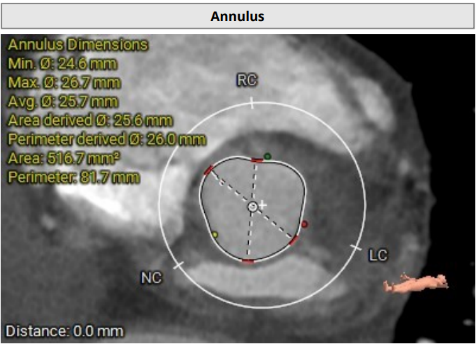

术前影像学评估 (3mensio)

瓣环及其他基本平面测量

术前影像学评估(Tavigator™AI术前辅助决策平台)